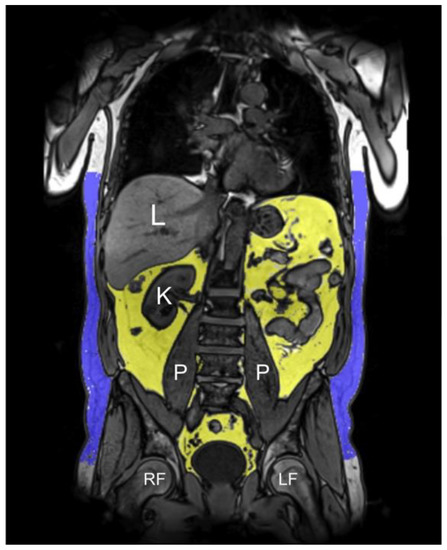

2.7. MRI-Based Fat Depots

3.3. Associations between Coffee Consumption and MRI-Based Fat Depots